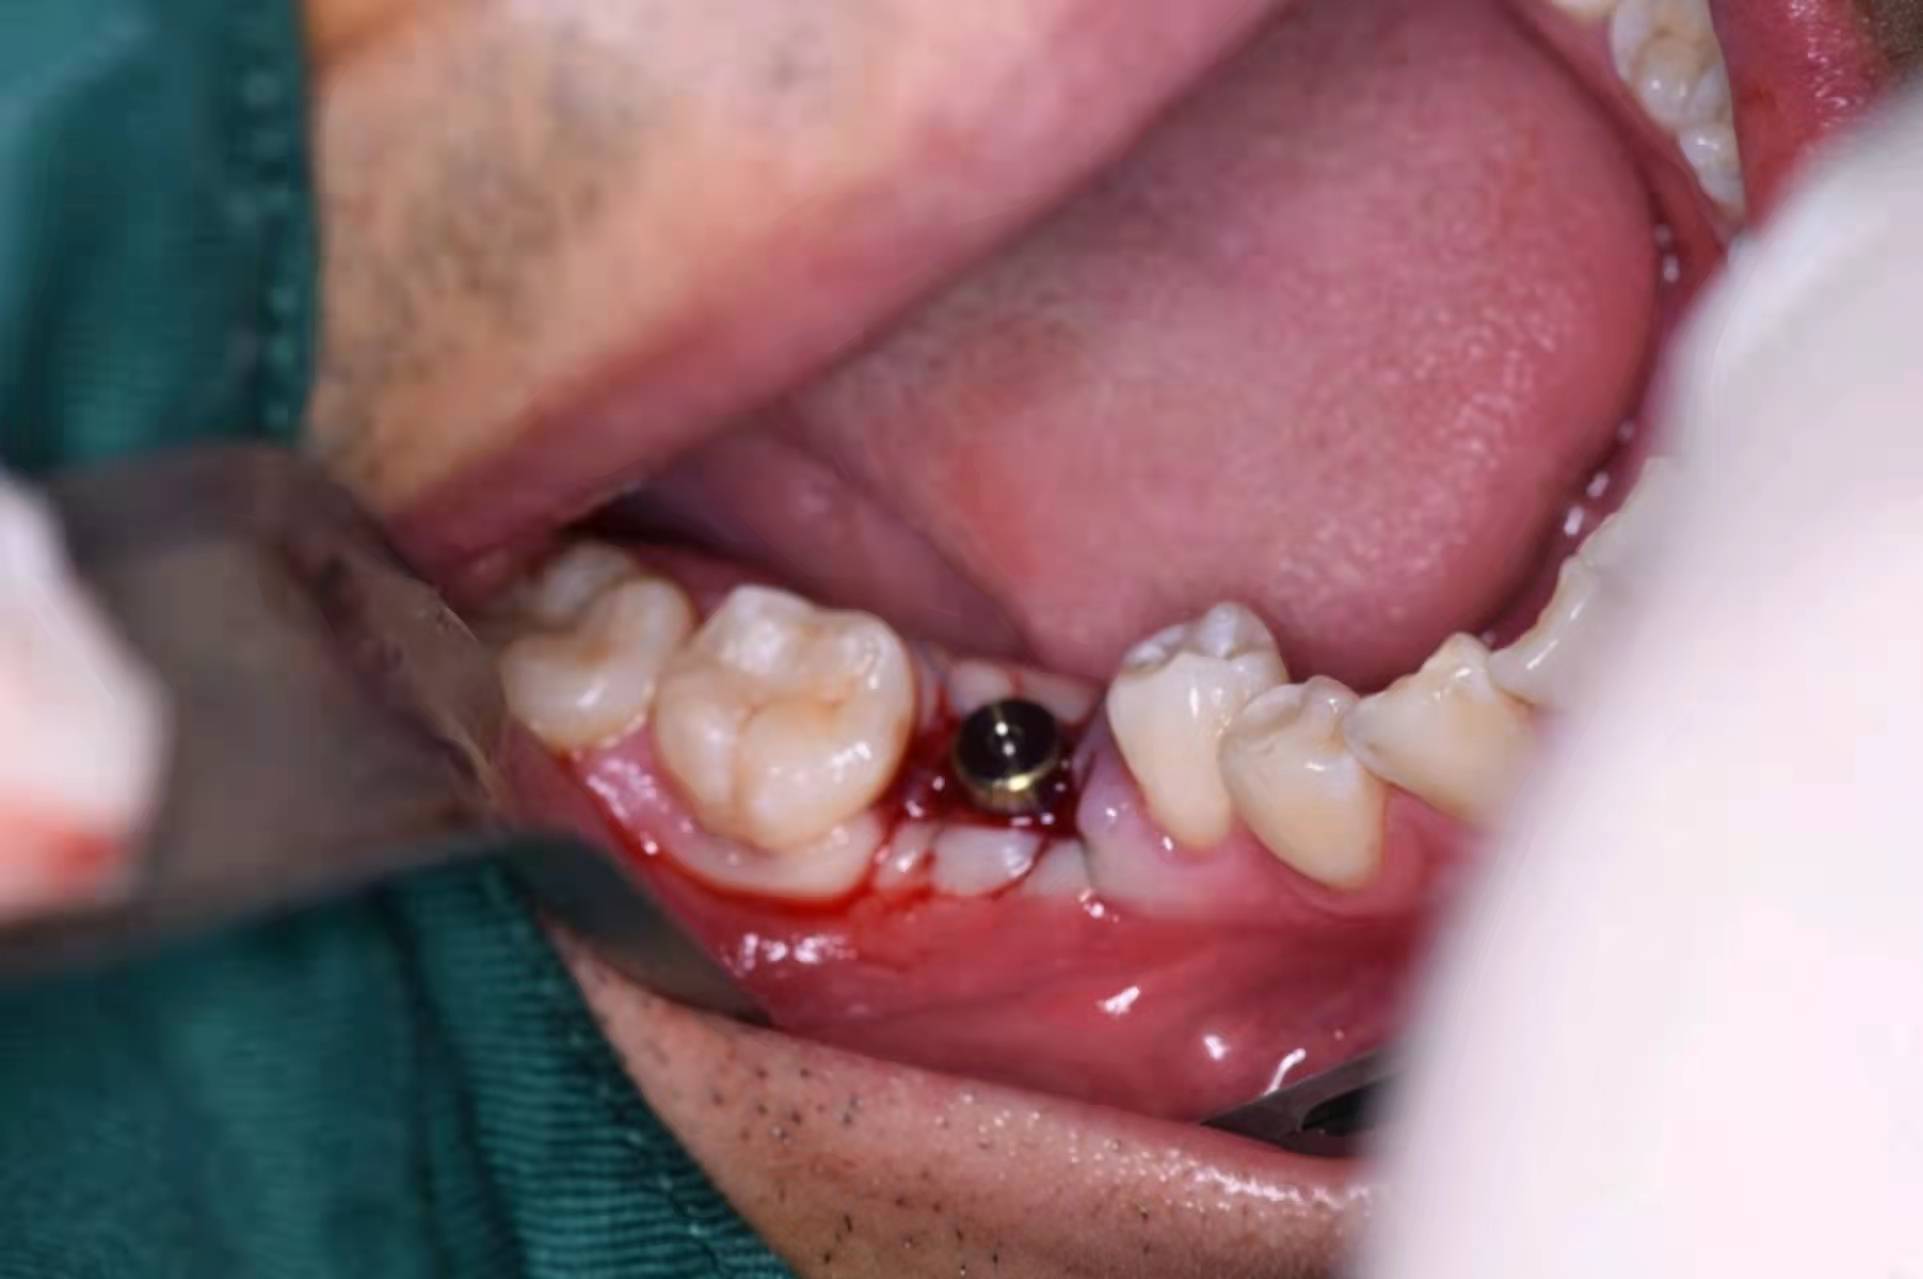

擰入愈合基臺:

術(shù)后CBCT圖: